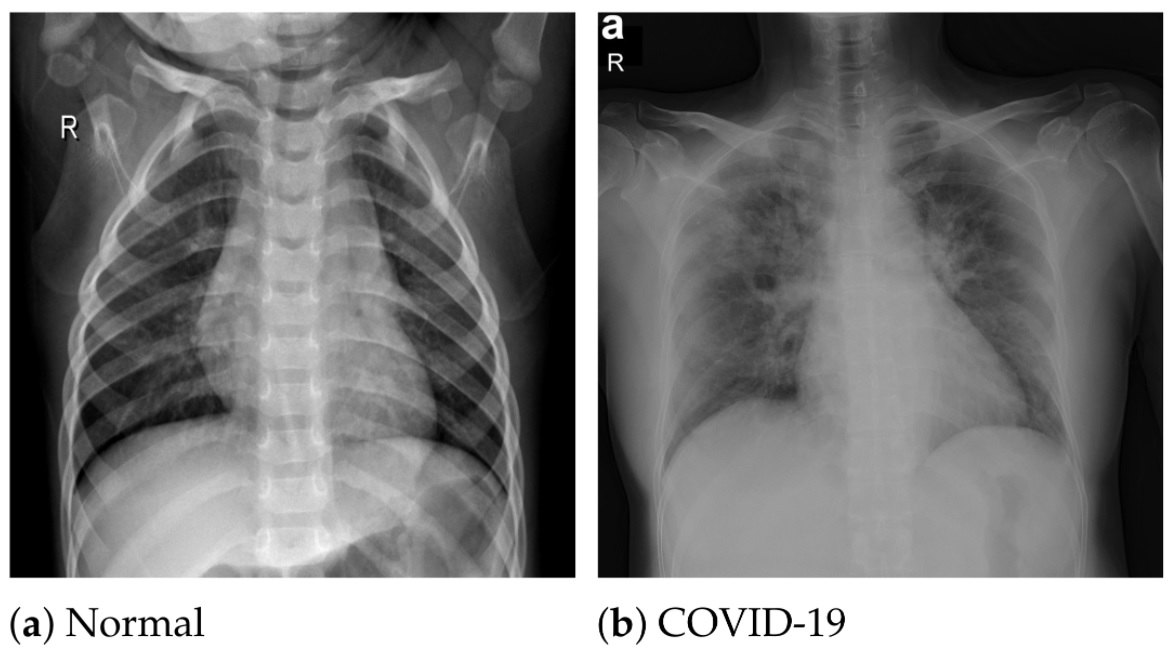

Za diagnosticiranje covida so raziskovalci z Univerze Zahodne Škotske uporabili rentgen. Nato so rentgenske slike primerjali z bazo 3.000 slik bolnikov s covidom, zdravih posameznikov in ljudi s pljučnico. Diagnozo so postavili z algoritmom globoke konvolucijske nevronske mreže, umetno inteligenco, ki običajno analizira slike, je objavila univerza.

Tehnika, ki uporablja umetno inteligenco in rentgenske posnetke, je bila v obsežni raziskavi pri odkrivanju virusa 98-odstotno zanesljiva. Za potrjevanje primerov so škotski raziskovalci uporabili rentgenske posnetke, ki so že široko dostopni.